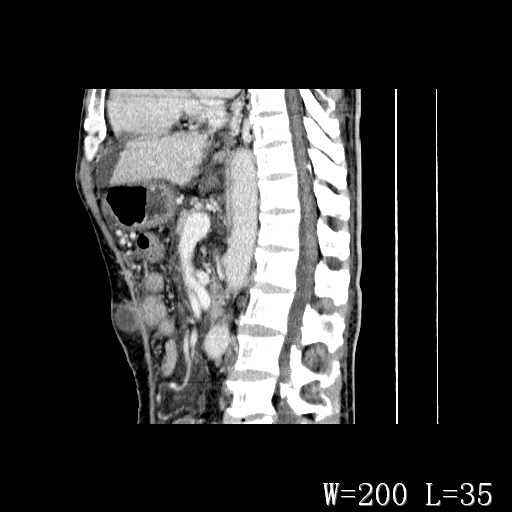

男,52岁,门脉高压断流术后1年,发现腹部肿物2月。

可能与门脉高压断流术有关,淋巴液回流受阻,腹壁淋巴囊肿?

1)前腹壁中线区(脐上方)囊性占位性病变,考虑淋巴囊肿。2)腹水。